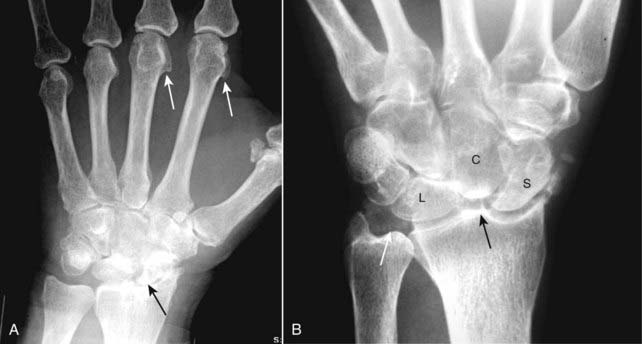

Figure 23-12 Calcium pyrophosphate deposition disease (CPPD).

CPPD arthropathy produces changes similar to osteoarthritis but differs from it in that CPPD affects joints not usually affected by primary osteoarthritis. A, Hook-shaped bony excrescences along the 2nd and 3rd metacarpal heads are a common finding in CPPD (solid white arrows). The radiocarpal joint is narrowed (solid black arrow). B, In the wrist, characteristic findings include calcification of the triangular fibrocartilage (solid white arrow), separation of the scaphoid (S) and the lunate (L) (scapholunate dissociation) and collapse of the capitate (C) toward the radius (solid black arrow) called scapholunate advanced collapse (SLAC).